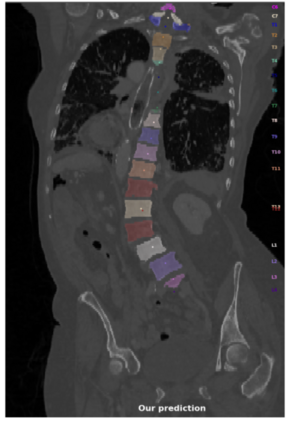

Vertebrae localization, segmentation and identification in CT images is key to numerous clinical applications. While deep learning strategies have brought to this field significant improvements over recent years, transitional and pathological vertebrae are still plaguing most existing approaches as a consequence of their poor representation in training datasets. Alternatively, proposed non-learning based methods take benefit of prior knowledge to handle such particular cases. In this work we propose to combine both strategies. To this purpose we introduce an iterative cycle in which individual vertebrae are recursively localized, segmented and identified using deep-networks, while anatomic consistency is enforced using statistical priors. In this strategy, the transitional vertebrae identification is handled by encoding their configurations in a graphical model that aggregates local deep-network predictions into an anatomically consistent final result. Our approach achieves state-of-the-art results on the VerSe20 challenge benchmark, and outperforms all methods on transitional vertebrae as well as the generalization to the VerSe19 challenge benchmark. Furthermore, our method can detect and report inconsistent spine regions that do not satisfy the anatomic consistency priors. Our code and model are openly available for research purposes.